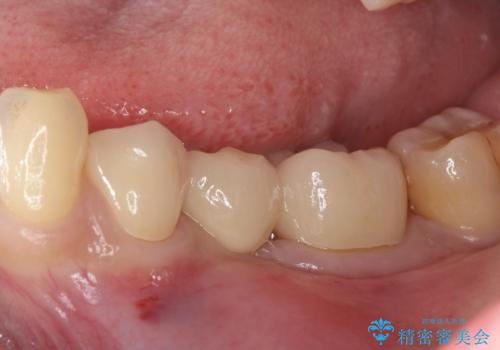

奥歯が痛い。乳歯を抜歯し、ブリッジによる咬合回復。

- 晩期残存した乳歯が痛くなったことを主訴に来院されました。

歯周病が進行していたため、抜歯を行い咬合回復を行いました。

インプラントは希望されなかったため、ブリッジにて治療を行っております。